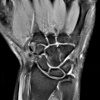

MRI of the wrist joint.

МРТ лучезапястного сустава. Высокоинформативный метод исследования лучезапястного сустава, основанный на измерении электромагнитного отклика ядер атомов водорода, подвергающихся воздействию радиоволн в магнитном поле. Результатом исследования является серия многослойных изображений. Методика позволяет визуализировать все структуры исследуемой области, распознавать дефекты кости, оценивать состояние хряща, мышц, связок и сосудов, расположенных в области сустава. Используется при воспалительных процессах, недавних поражениях, последствиях травматических поражений, доброкачественных и злокачественных новообразованиях, нарушениях развития, ограничении подвижности и болевом синдроме неясного генеза.